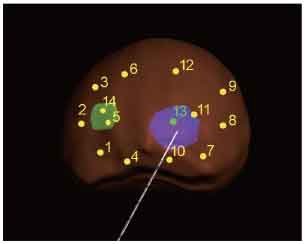

MRI-Ultrasound Fusion in Transperineal Prostate Biopsy

Bi-planar MRI-Ultrasound real-time fusion

3D navigation and tracking

Automatic visualization of lesions and systematic targets